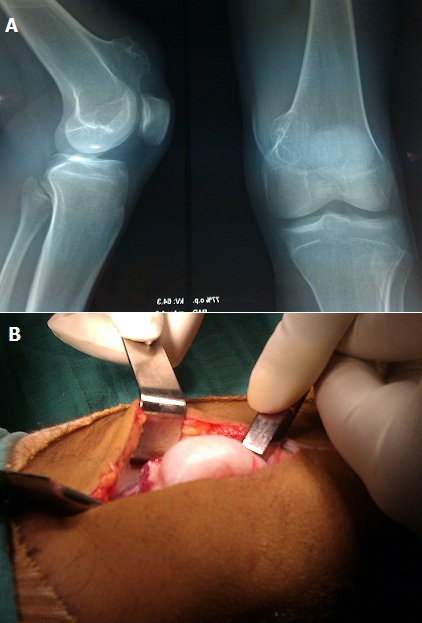

Exostose géante de l’extrémité inférieure du fémur

Les exostoses sont des formations osseuses développées à la surface des os et qui sont recouvertes par du cartilage. Il s'agit de la plus fréquente des tumeurs bénignes après les fibromes non ossifiant et les lacunes métaphysaires. Elles se localisent préférentiellement sur le versant métaphysaire du cartilage de croissance fertile. Sur le plan physiopathologique l'hypothèse d'une bascule à 90° d'un fragment du cartilage de croissance est appuyée par les travaux expérimentaux d'Ambrosia et Ferguson. La découverte fortuite est une circonstance diagnostique fréquente quand l'exostose est de petite taille, elle est alors constatée lors d'un bilan radiologique réalisé pour un autre motif. Les formes symptomatiques sont représentées par les formes douloureuses, celle-ci peut avoir plusieurs explications : fracture de la base de l'exostose, bursite, distension des parties molles. Les formes volumineuses, c'est le cas de notre patient, doivent suspecter chez l'adulte une dégénérescence. Le diagnostic de certitude est fait par la radiographie standard qui montre une image d'addition sessile ou pédiculée, précise son siège, son volume et la présence de micro calcifications. La TDM a peu d'intérêt dans l'exploration de l'exostose solitaire. L'IRM a pour intérêt d'étudier les rapports de la tumeur avec les éléments nobles vasculo nerveux dans le cadre d'un bilan pré opératoire. La confirmation diagnostique est anatomopathologique. Le risque de dégénérescence sarcomateuse est évalué dans la littérature à 1% et se fait le plus souvent vers un chondrosarcome, doit être suspecté quand l'exostose augmente rapidement de volume. Le traitement est chirurgical et consiste en une résection complète de l'exostose à partir de sa base, la biopsie préalable n'est pas systématique dans la forme typique